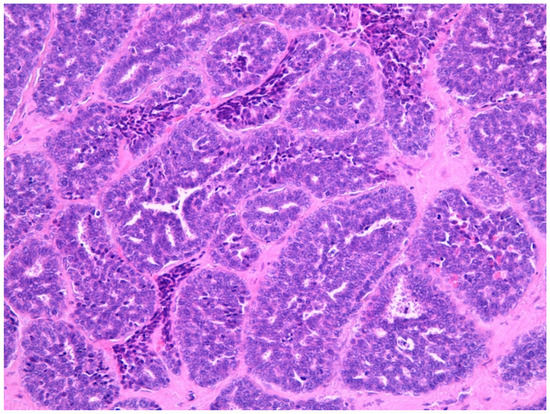

4.5. Intestinal Adenocarcinoma

4.9. Olfactory Neuroblastoma (ONB)